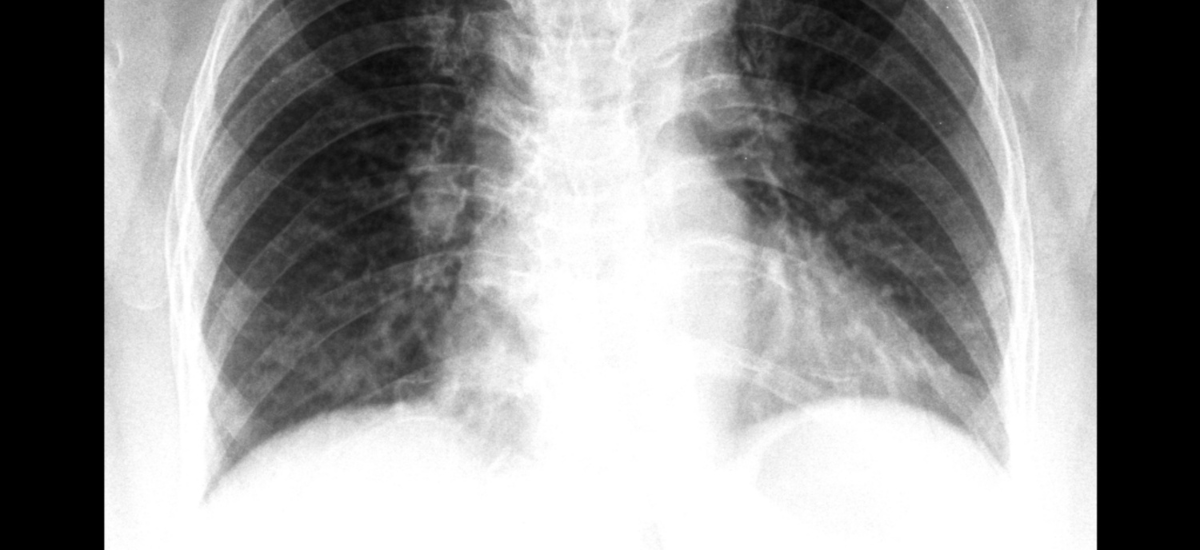

For Accurate Diagnosis and Staging: The specific ICD-10 code for lung cancer works hand-in-hand with your pathology report and imaging (like CT scans) to create a complete clinical picture. It helps your team accurately stage the cancer, which is the single most important factor in determining your treatment options and prognosis.